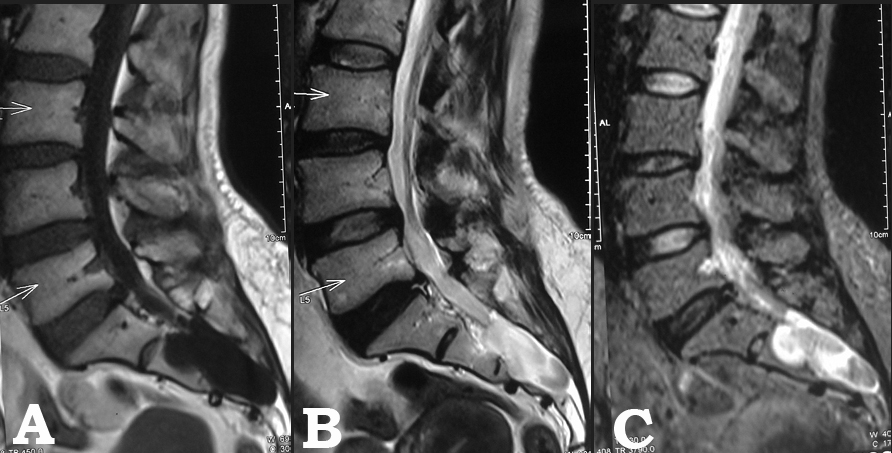

Sacral arachnoid cyst presenting as chronic low back pain

Agrawal, A., Santhi, V., & Rao, G. M. (2014). Sacral arachnoid cyst presenting as chronic low back pain. Bangladesh Journal of Medical Science, 14(1), 106–108. https://doi.org/10.3329/bjms.v14i1.16191